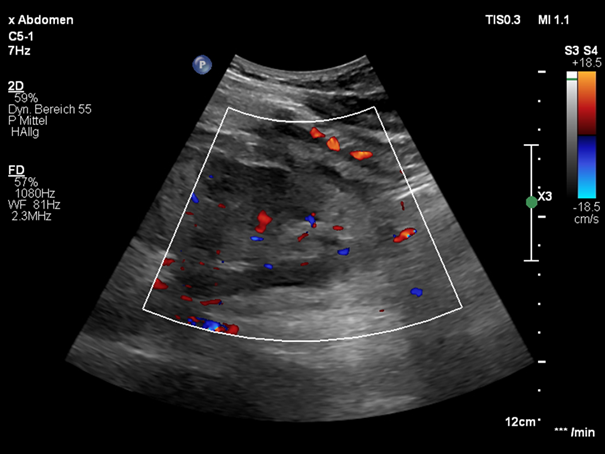

The Color Doppler and Micro-flow Imaging examinations depicted a ying-yang swirling motion blood flow within the lesion. Because an active bleeding could not be excluded by color Doppler, the examination was complemented with CEUS. (Figure 2)

Figure 2 Delimitation of the vascularized renal lesion (arrow) on color Doppler (a) and MFI (b).